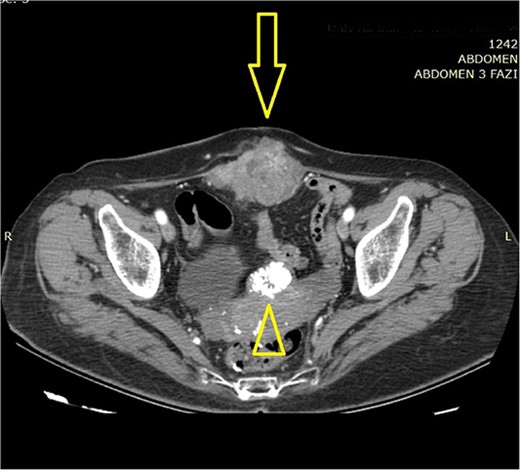

A 73-year-old female patient was admitted to our hospital due to the existence of a tumor in the abdominal wall proved to be a metachronous adenocarcinoma metastasis. In October 2015, the patient was treated for rectosigmoid adenocarcinoma when rectosigmoid resection with primary anastomosis was performed. Pathology report revealed tumor stage I (pT2, pN0, pM0, pL0, pV0, pR0, G2, NG2). Only three lymph nodes were harvested and reported to be negative by the pathologist. Nevertheless, the oncologist decided not to initiate adjuvant chemotherapy, and recommendations for routine outpatient check-ups were advised. Two postoperative routine colonoscopies with normal findings were performed (in 2016 and 2022). Shortly after the second colonoscopy (in September 2022), elevated values of serum tumor markers were detected: Carcinoembryonic antigen (CEA) value of 15.2 ng/mL and Carbohydrate antigen (Ca) 19–9 value of 47.3 U/mL. The oncologist initiated adjuvant treatment with eight cycles of oxaliplatin and capecitabine. In March 2023, the additional elevation of markers followed (CEA value of 58.64 ng/mL, Ca 19-9 value of 665.12 U/mL, and Cancer antigen 15-3 value of 32.5 U/mL). In June 2023, serum marker levels decreased (CEA value of 35.5 ng/mL and Ca 19-9 value of 147 U/mL). Physical examination on routine follow-up revealed a palpable painless mass in the midline suprapubic region without skin involvement. Abdominal computerized tomography presented a solid tumor mass in the abdominal wall with dimensions of 70 × 40 × 80 mm and it was described as a suspected metastatic deposit by the radiologist (Figs 1 and 2). Core biopsy under ultrasonography guidance confirmed the presence of metastatic adenocarcinoma ˃7 years after the primary colon cancer surgery. A decision upon surgical removal was brought. The lesion was excised (Figs 3 and 4) and the defect of the abdominal wall was reconstructed by the use of composite mesh (Fig. 5). The postoperative course was uneventful and the duration of stay was 7 days. The pathology report confirmed the presence of metachronous metastasis from colon adenocarcinoma. Metastasis was measured to be 10 × 6 × 5 cm, completely occupied by a neoplastic infiltrate (Fig. 6). Immunohistochemistry staining showed positivity on Caudal-type homeobox 2 (CDX2) and Cytokeratin 20 (CK20) thus proving the origin of the metastatic deposit from colorectal adenocarcinoma (Fig. 7A–C).

Abdominal computerized tomography (axial scan) shows a tumor in the abdominal wall (arrow) with the secondary finding of calcified uterine myoma (arrowhead).